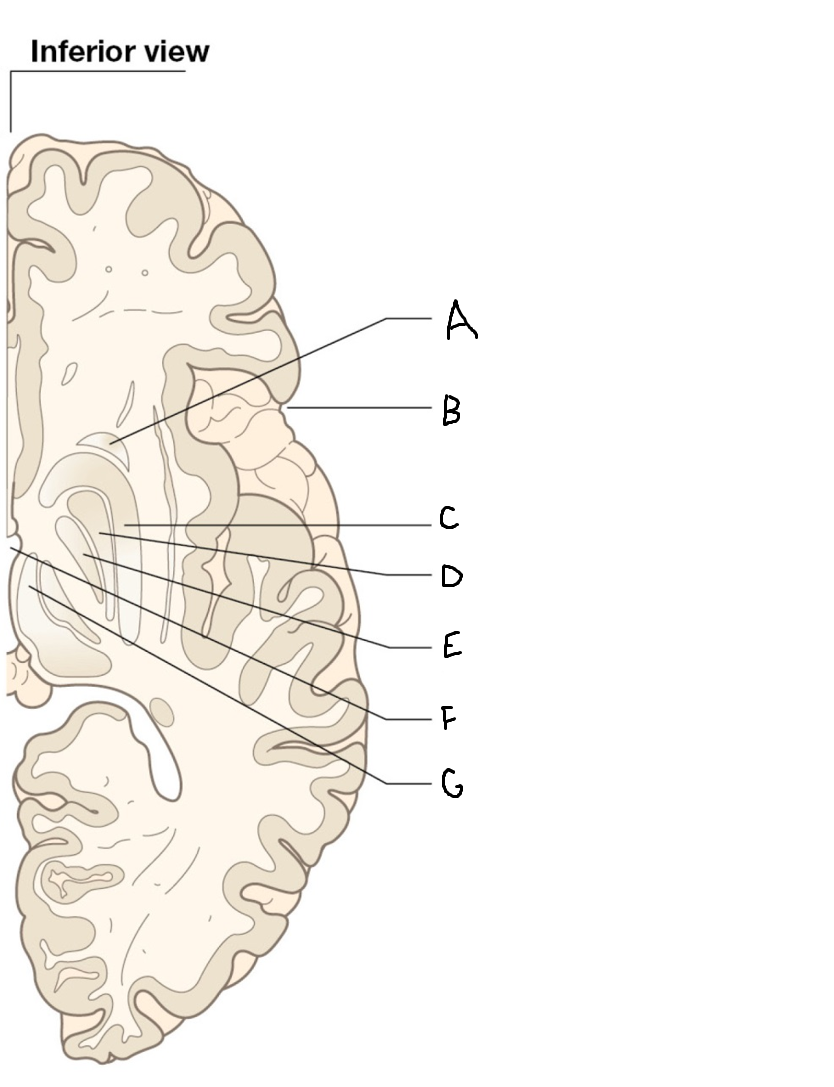

B

anterior horn of lateral ventricle

C

head of caudate nucleus

D

internal capsule (anterior limb)

E

putamen

F

globus pallidus

G

Thalamus

H

External capsule

I

internal capsule (posterior limb)

J